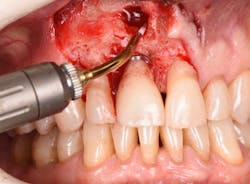

Figure 20: An osteotomy was done to access apical area of implant No. 8 utilizing the Er:YAG laser at 20 pps/70 mJ. The then-exposed area was irradiated using a combination of detoxification and biostimulation of the bone and implant to prepare the area to receive a bone graft.